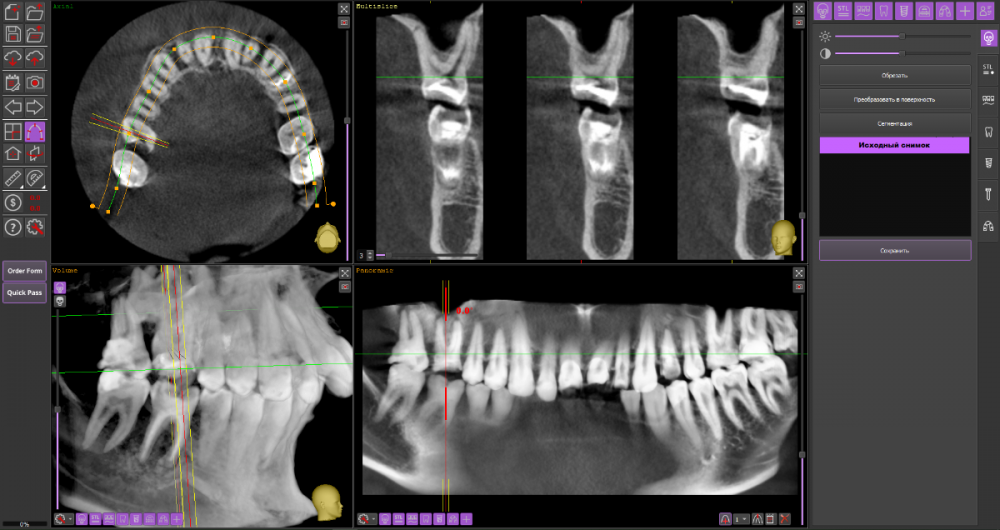

Добрый вечер, уважаемые специалисты. Подскажите, пожалуйста, есть ли возможность избежать удаления верхней 6-ки справа и использовать культевую вкладку + коронку для протезирования? Заранее спасибо за ответы. КТ: https://drive.google.com/drive/folders/17DOY2HNbp9x-5vxpit8V9hBL8D88hrAt?usp=sharing

16_1.thumb.png.bb12ffa7175f4bd0f7f85bb8f69ea174.png

16_2.thumb.png.9dafe1ce7b90f3a15660ac669b24eb3e.png

На мой взгляд, зуб 16 вполне можно сохранить при условии адекватного лечения корневых каналов.

А вот зуб 17 перелечить маловероятно.